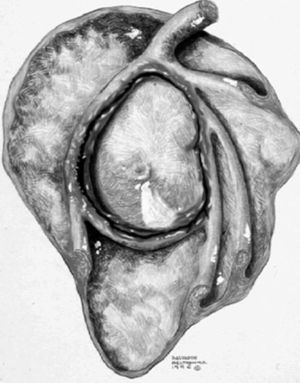

Lesión de Bankart

La lesión de Bankart se produce durante una dislocación anterior e inferior de la cabeza humeral, con impactación de la misma contra el borde anteroinferior de la glenoides, causando un arrancamiento del LG con rotura capsuloperióstica. Al mismo tiempo, se produce frecuentemente una fractura por impactación de la cabeza humeral (lesión de Hill Sachs) (fig. 9). En ocasiones, dicha lesión se acompaña de una fractura del borde anterior e inferior de la glenoides (Bankart óseo).

Fig. 9.--Lesión de Bankard y Hill-Sachs. Artrorresonancia axial T1, donde se observa un desprendimiento completo del labio glenoideo (flecha larga en A) con una rotura capsuloperióstica (cabezas de flecha en A). Nótese la fractura por compresión del margen posterosuperior de la cabeza humeral, representando una lesión de Hill-Sachs (flechas en B).